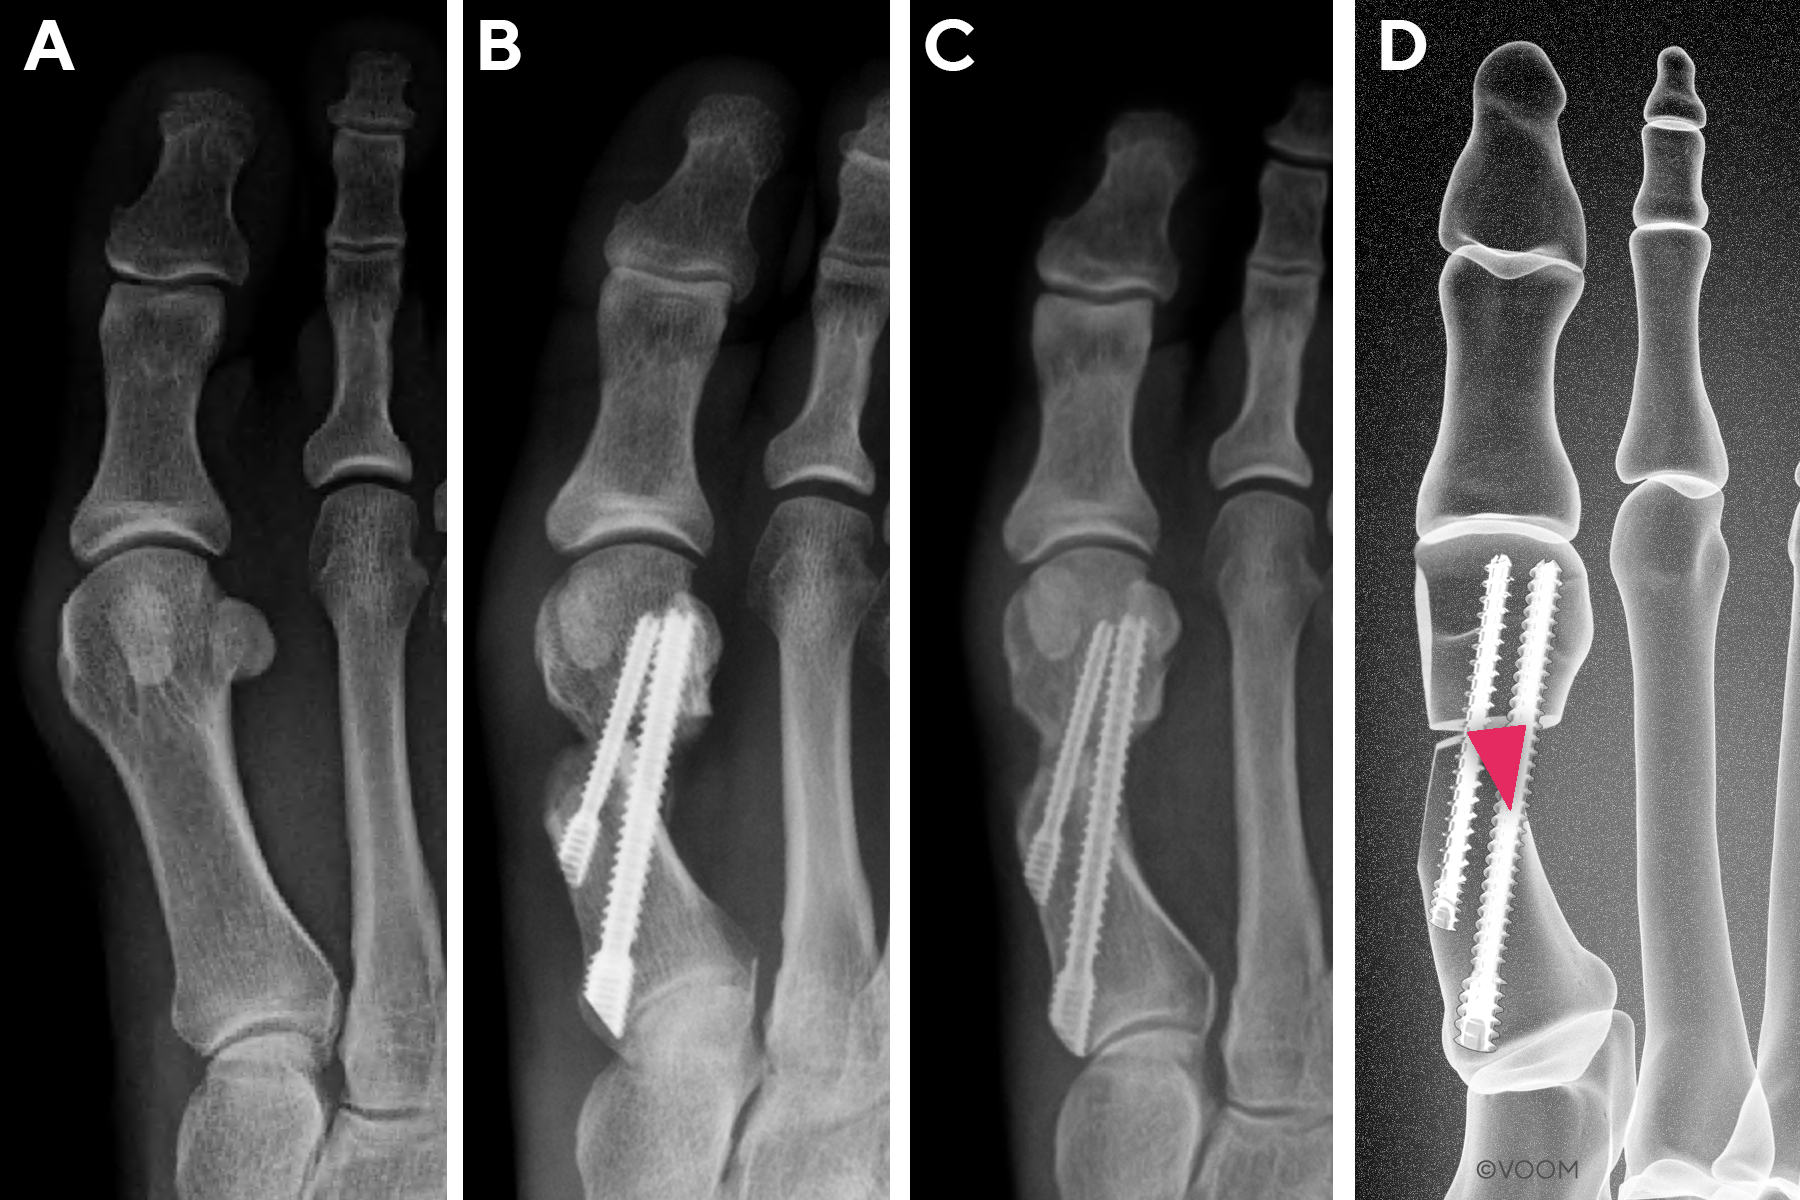

First Metatarsal Regeneration Type III: Robust callus formation with first metatarsal regeneration (Figure 4).

_type_iii.jpg)